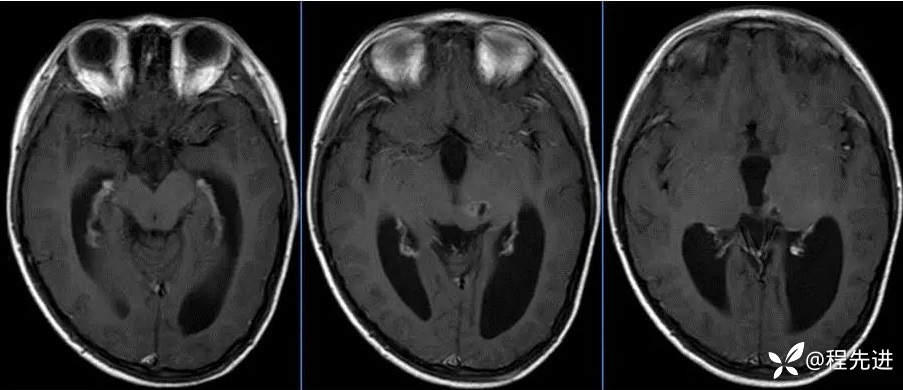

MR